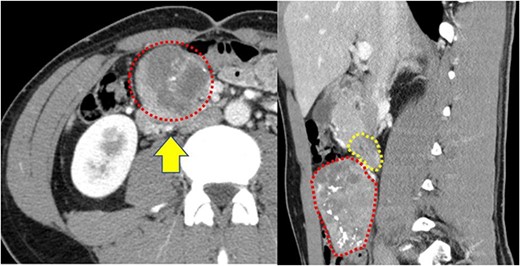

A 22-year-old man was referred to our department with the chief complaint of nausea and vomiting. An abdominal examination revealed a mass with poor mobility and elastic hardness on the right side of the navel. Further evaluations using abdominal ultrasonography revealed an ~83 × 51 × 49 mm well-defined, oval, hypoechoic, and heterogeneously enhanced mass with a strong echo. A contrast-enhanced computed tomography scan showed a well-defined, heterogeneous enhancement with calcification. The tumor pushing the transverse part of the duodenum was present on the ventral ileocolic vessels and measured ~6 cm (Fig. 1). Magnetic resonance imaging was performed to confirm invasion of other organs. All of the above examinations suggested that the tumor had not invaded other organs, especially the duodenum. Esophagogastroduodenoscopy revealed no lesions in the duodenal lumen. However, the duodenum was pushed by a mass outside the lumen (Fig. 2).

(a) Contrast-enhanced computed tomography reveals a well-defined heterogeneous enhancement mass with calcification (red dotted box); the mass is present on the ventral ileocolic vessels (yellow arrow); (b) the transverse duodenum (yellow dotted box) is pushed by this tumor (red dotted box).